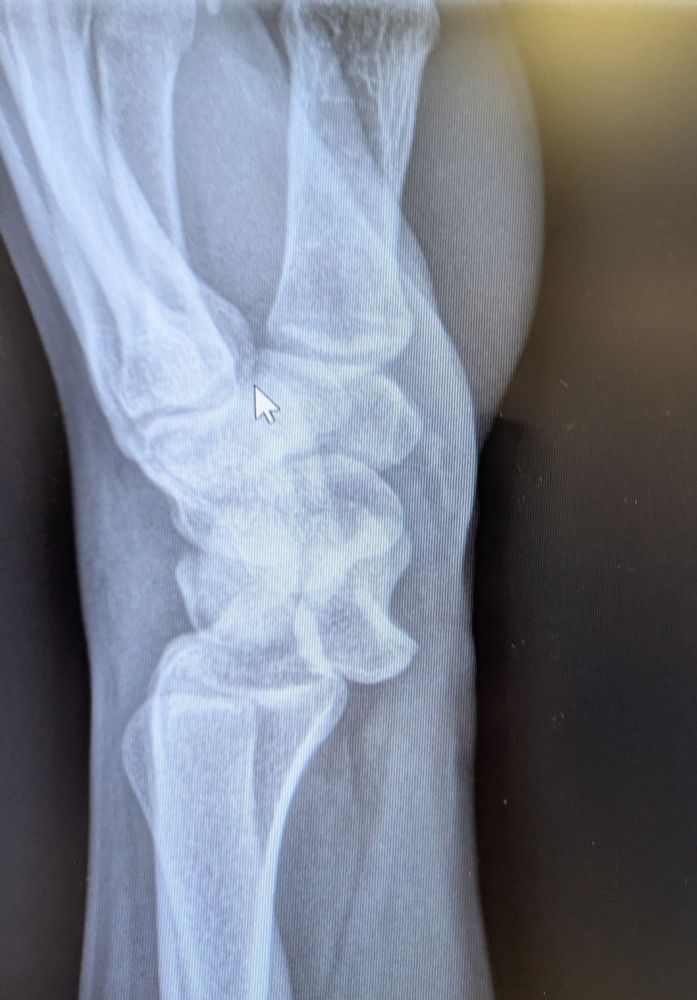

Lunate dislocation

"Spilled teacup sign"

#medsky #orthosky #emedsky